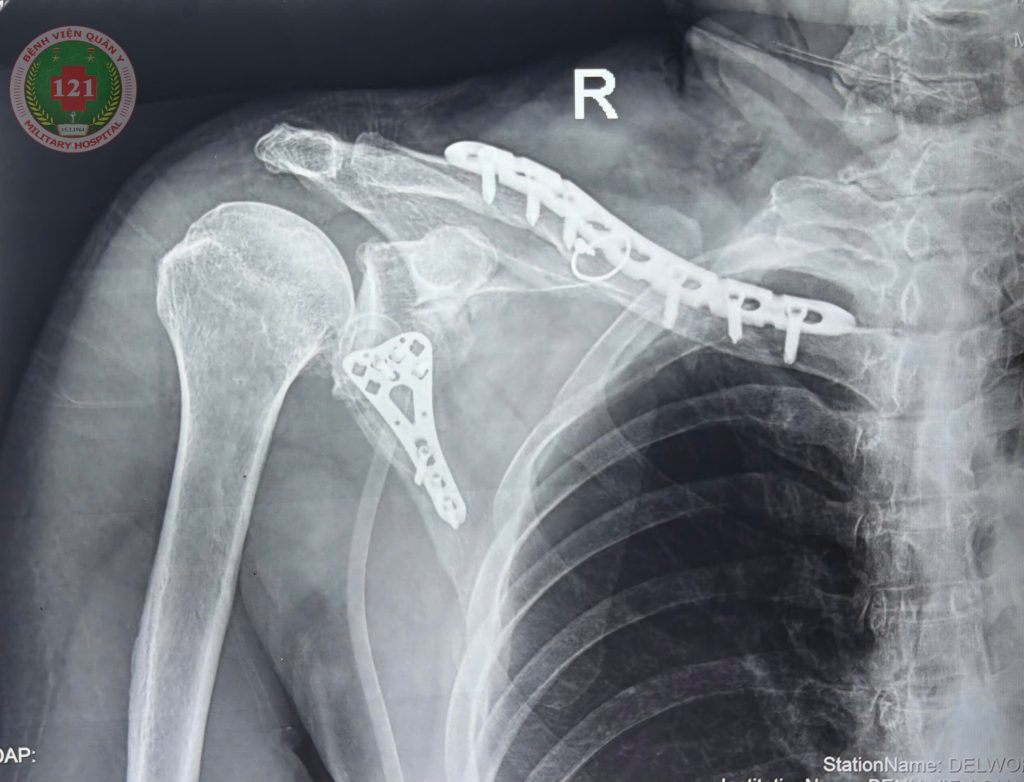

THỰC HIỆN THÀNH CÔNG CA PHẪU THUẬT NẸP VÍT KHÓA KẾT HỢP XƯƠNG BẢ VAI VÀ XƯƠNG ĐÒN CHO MỘT NAM BỆNH NHÂN 74 TUỔI

Ngày 24/01/2026, với sự hỗ trợ chuyên môn từ Bệnh viện Chấn thương chỉnh hình TP. Hồ Chí Minh, Bệnh viện Quân y 121 đã thực hiện thành công ca phẫu thuật nẹp vít khóa kết hợp xương bả vai và xương đòn cho một nam bệnh nhân 74 tuổi có tiền sử tăng huyết áp. Bệnh nhân nhập viện cách đây 09 ngày sau một vụ tai nạn giao thông, trong tình trạng vai phải sưng nề, bầm tím, vận động hạn chế. Bệnh nhân được chụp Xquang và chụp cắt lớp vi tính dựng hình 3D xác định gãy 1/3 giữa xương đòn phải, xương bả vai phải và 03 xương sườn. Sau khi được thăm khám và hội chẩn, các bác sĩ xác định cần tiến hành phẫu thuật nẹp vít khóa kết hợp xương bả vai và xương đòn để phục hồi chức năng vận động cho bệnh nhân.

Nhờ sự phối hợp chặt chẽ giữa đội ngũ bác sĩ Bệnh viện Quân y 121 và sự hỗ trợ kỹ thuật từ Bệnh viện Chấn thương chỉnh hình TP. Hồ Chí Minh, sau 03 giờ ca mổ đã thành công tốt đẹp, đảm bảo an toàn và tuân thủ đúng quy trình chuyên môn. Sau phẫu thuật, bệnh nhân có triển vọng phục hồi vận động sớm, giảm thiểu biến chứng và nâng cao chất lượng cuộc sống.